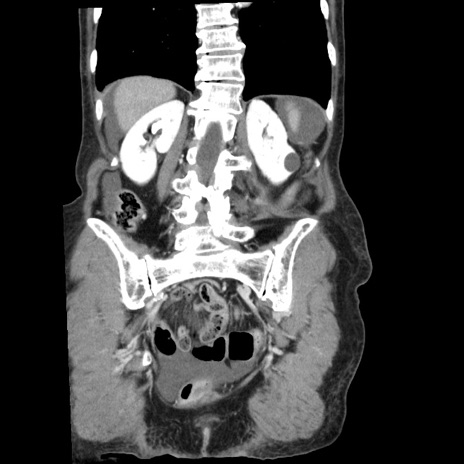

症例1(冠状断像)

【症例】80歳代女性

【主訴】腹痛

【現病歴】8時間前から腹痛あり来院。

【既往歴】糖尿病、脂質異常症、子宮体癌にて子宮全摘術

【身体所見】意識清明・会話良好だが腹痛で苦悶様、全腹部にわたって反跳痛と圧痛あり

【データ】WBC 13600、CRP 0.14、LDH 224、CK 90